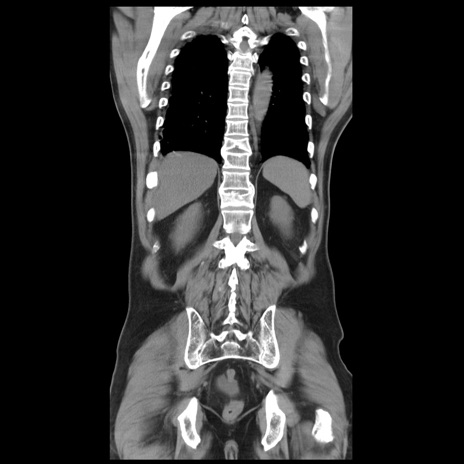

症例20(冠状断像)

【症例】 60歳代男性

【主訴】 腹部膨満、嘔吐

【現病歴】5日前頃より倦怠感を認め食事量減少し4日前の朝嘔吐、食事摂取困難となった。 3日前近医受診し点滴施行され整腸剤などを処方された。 当日他院を受診し、腹部膨満著明、炎症反応の上昇(CRP10.8、WBC11200)あり、紹介受診となる。

【身体所見】 意識JCS1 受け答えがはっきりしないBP 111/57mHg、 P 67bpm、、BT35.2°C、SpO2 97%(RA)、 腹部:膨隆、打診で鼓音あり、全体的に圧痛有り、腸蠕動音(-)、反跳痛ははっきりせず。

【データ】WBC 11400、CRP 14.20